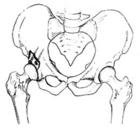

股骨头就是支撑身体上半部分的两根骨头,具体位置在骨盆下方,骨盆那里一边一个髋臼,两个股骨头正好和髋臼配合,起到支撑上体的作用。如果从外面看就是在臀部的后下方。股骨是人体最重要的骨骼,股骨头更为重要,人的直立行走、活动、劳动都依靠股骨头的支撑作用。所以股骨头也是最容易受伤的部位。

⑤X线表现。骨纹理细小或中断,股骨头囊肿、硬化、扁平或塌陷。

外伤导致股骨头坏死的原因在于供应股骨头的血管受损所致,如侧方骨骺血管受损。这些血管受损后,股骨头全部或部分失去血运,伤后血运阻断8小时后即可造成缺血坏死。由此可见,在有移位的股骨颈骨折中,骨坏死很早即可发生。股骨头缺血坏死占股骨颈移位骨折的85%和无移位骨折的15%—25%。有报告称,在粗隆间骨折穿针后也有股骨头缺血坏死发生,这是由于股骨头穿针所致,因为在穿针过程中可能伤及外侧骨骺血管(穿针由股骨头侧上方或后方进入股骨头)。这个血管的损伤可造成股骨头局部缺血坏死,最后在股骨头上部负重部位发生塌陷。